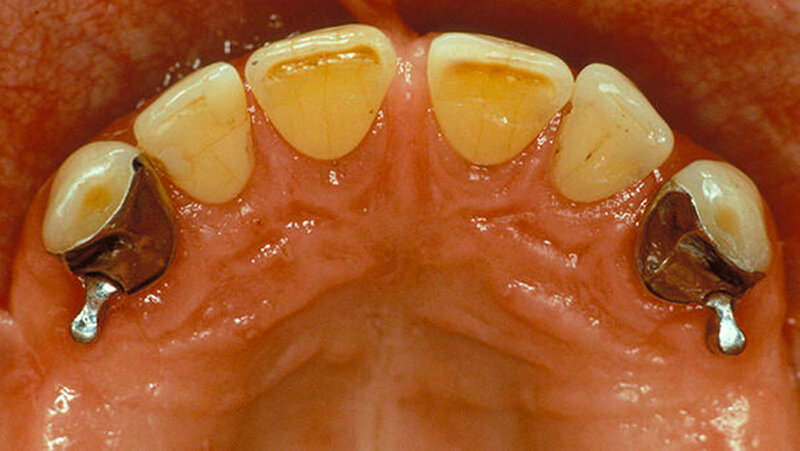

Beispiele für individuellen ZE

Die Jahrestagung der Deutschen Gesellschaft für Prothetische Zahnmedizin und Biomaterialien (PGPro) in Ulm geht der Frage nach, welche Versorgungskonzepte - mit guten Langzeitergebnissen - individuell und preiswert machbar sind. Gute Beispiele finden Sie in unserer Bilderstrecke!